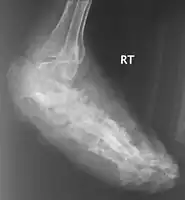

X rays and ultrasonography may be carried out to assess the extent of the disease. X rays findings are extremely variable. The disease is most often observed at an advanced stage that exhibits extensive destruction of all bones of the foot. Rarely, a single lesion may be seen in the tibia where the picture is identical with chronic osteomyelitis. Cytology of fine needle aspirate or pus from the lesion, and tissue biopsy may be undertaken sometimes.[9] Some publications have claimed a "dot in a circle sign" as a characteristic MRI feature for this condition (this feature has also been described on ultrasound).[12]

X-ray foot: mycetoma